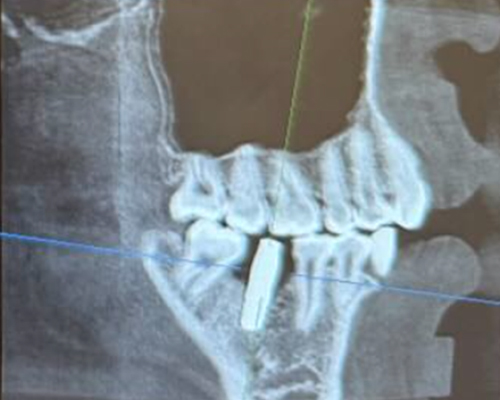

米国の技術×専属技工士×精密機器のフル活用で「短期治療」を実現!

米国の先端治療を安価で

インプラント、マウスピース矯正、小児矯正の歯医者なら「ALBA歯科&矯正歯科」。東京・神奈川・海外を中心に26医院を展開する当グループの専門治療をご案内します。年間1,000症例以上の「世界レベル」オペを実施しているインプラント治療では最安で税込99,800円~の低価格を実現。目立たずメンテナンスも容易と好評の透明なマウスピース矯正は月3,300円からご提供が可能です。重度の歯周病でも徹底的な検査と滅菌で再発を防止し、包括治療で早期解決します。低価格・低リスクの「小児専門」矯正治療を実現、通常100万円ほどかかるワイヤー矯正と比べ、半額程度の費用で矯正治療がおこなえます。年中無休で土・日・祝日も診療中。朝10時台から夜20時(鶴ヶ峰院、上永谷院は19時)まで受診可能。

年間1,000症例以上の 「世界レベル」オペ実施

最安で税込99,800円~の低価格を実現